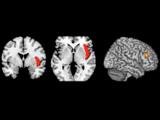

Исследователи из университетов Манчестера и Ливерпуля выяснили, что те области мозга, которые отвечают за удовольствие, чрезвычайно активны у людей с биполярным расстройством...